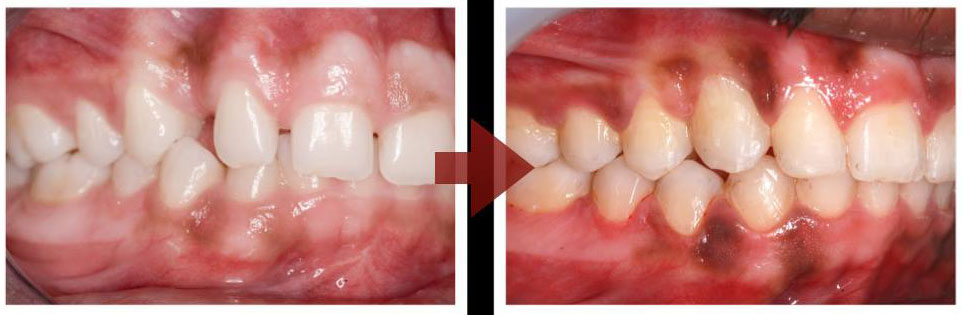

A highly motivated student decided to get his impacted canine (a canine stuck inside the jawbone) treated with Orthodontics..the journey was long but the destination was beautiful!!! Impossible is nothing!!!

They can cause facial asymmetry and an unbalanced smile… |

The missing Canine |

An orthodontist can help, to get the canine back into its rightful position |

To get a beautiful balanced smile!!! |